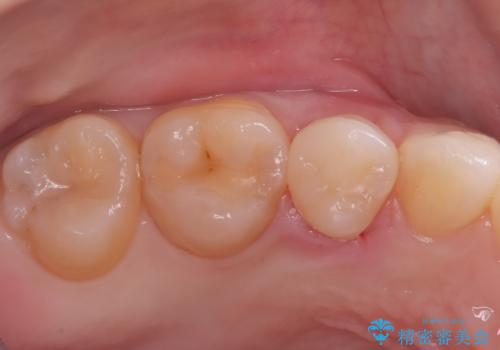

後日、歯の色調に合わせてオーダーメイドで作製されたセラミックインレーを装着。セラミックは天然歯のような透明感があるため、修復した箇所がどこかわからないほど自然な仕上がりとなりました。

また、セラミックは汚れ(プラーク)が付きにくく、経年劣化による変色もほとんどないため、再発リスクを抑えつつ、長期的に白く美しい状態を維持することが可能です。機能・審美の両面で、患者様にご満足いただける結果となりました。